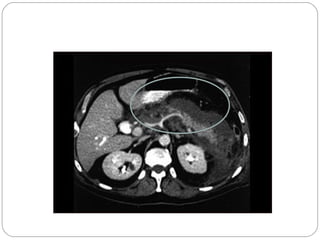

Abceso Pancreático

Quiste Pancreático

Absceso

Es una colección bien circunscrita de pus con mínima o

ninguna necrosis. Puede ocurrir en ataques inicialmente

graves asi como en los que inician como leves. También

se usa la bacteriología percutánea como único medio de

diagnóstico